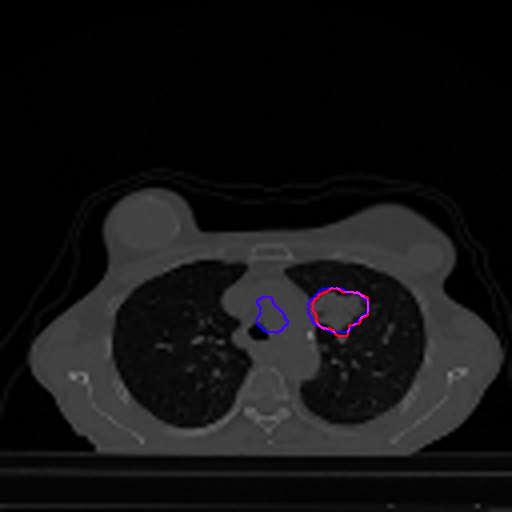

A qualitative analysis of our results reveals the strengths and weaknesses of our proposed model. In most cases, regardless of the size of the ground truth, our model predicts the tumor shapes very well. This is evident from Figure 4 where the ground truth and the prediction (by Deeply Supervised MultiResUNet) are shown in red and blue respectively. Although the tumors are in various arbitrary locations within the lung and appear in diverse sizes, the red and blue margins appear to coincide almost perfectly.

Figure 5 shows a comparison between predictions by the MultiResUNet model and Deeply supervised MultiResUNet model. It can be seen that the latter can delineate the tumor edges more accurately than the former. The ground truth (shown in red) and the prediction (shown in blue) have a more consistent alignment with each other in Deeply Supervised MultiResUNet’s prediction.